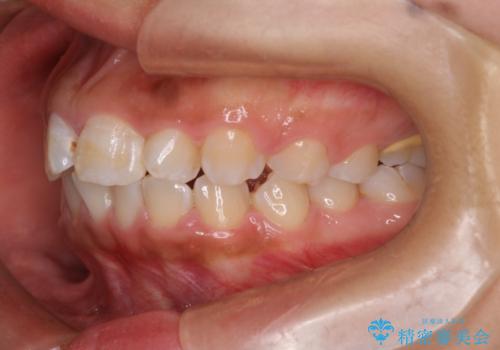

マウスピース矯正で前歯のガタツキを改善! ワイヤー矯正併用でかみ合わせもしっかり治します

- 前歯のガタツキが気になると来院されました。

マウスピース矯正治療を選択しました。

前歯のガタツキを改善する治療法として、マウスピース矯正が適していることが多いです。

マウスピース矯正は、金属製のブラケットやワイヤーを使用せずに、透明なマウスピースを装着して歯を移動させる方法です。そのため、目立たず、痛みも少ないです。

この症例では、奥歯のかみ合わせの改善を目的にワイヤー矯正を併用しました。奥歯のかみ合わせをより緊密にするため、また短期間に治療するためにはワイヤー矯正が適していることがあります。